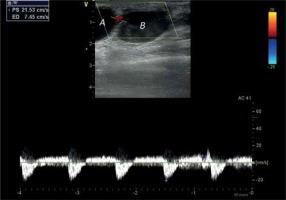

Figure 2

Pseudoaneurysm entry with blood outflow from the radial artery and patent distal part of a vessel

A – first chamber, B – second chamber, RA – radial artery.